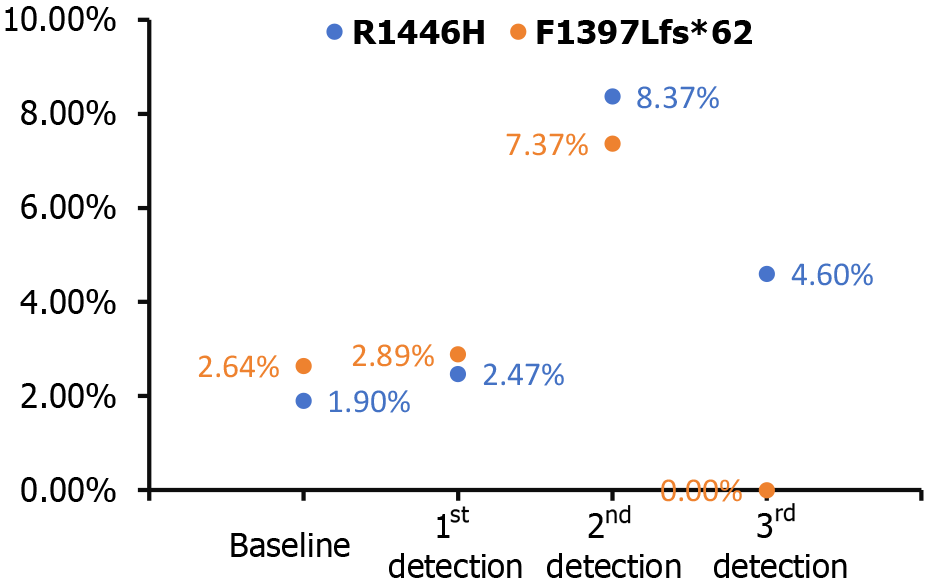

In this case of a patient with LS and multiple colorectal neoplasms, the optimal treatment strategy is one that is both personalized and multidisciplinary. It integrates precision medicine with immunotherapy and molecular surveillance to achieve the best possible outcomes. The initial treatment plan might include a combination of chemotherapy drugs, such as oxaliplatin and capecitabine in the XELOX regimen, alongside PD-1 monotherapy with sintilimab. However, due to drug-induced complications, such as a rash, the treatment may be refined to include pembrolizumab, another PD-1 inhibitor[10]. Moreover, the immunotherapy-related skin reaction is now considered a positive prognostic sign, suggesting a favorable response to the therapeutic intervention[11]. This individualized treatment approach, guided by the patient’s genetic profile and clinical features, has resulted in marked tumor regression and alleviation of symptoms, including hematochezia. Additionally, the tumor has achieved a complete clinical response, indicating that traditional imaging diagnostics and their predictive value may be diminished in this context. The heightened sensitivity to PD-1 blockade in LS patients has proven to be highly effective, and this is further enhanced by the vigilant monitoring of MRD. The detection of CREBBP mutations through MRD surveillance has revealed two specific alterations: R1446H and F1397 Lfs*62. R1446H is a missense mutation in exon 26, where the 1446th amino acid changes from arginine to histidine. F1397 Lfs*62 is a frameshift mutation caused by a deletion at position 4188 of exon 25, resulting in a shifted reading frame and protein truncation. This finding indicates potential molecular progression of the tumor, prompting a strategic adjustment to the treatment protocol by incorporating capecitabine alongside pembrolizumab. CREBBP, a gene associated with oncogenic activity, signifies the presence of a molecular signature that may portend a propensity for tumorigenesis, underscoring the importance of personalized therapeutic interventions. This intervention has successfully reduced circulating CREBBP levels, allowing for the continuation of effective monotherapy (Figure 4).

Our case underscores the critical role of a multidisciplinary therapeutic strategy in the management of LS-associated CRC. The incorporation of precision medicine, including personalized chemotherapy and immunotherapy, was instrumental in our patient’s management. Notably, MRD surveillance was crucial, enabling the detection of a CREBBP mutation that prompted a strategic shift to pembrolizumab, leading to sustained clinical complete remission. This underscores the importance of MRD surveillance in guiding real-time treatment adjustments and underscores the potential of precision medicine to enhance outcomes for patients with hereditary cancer syndromes. As the field of precision medicine advances, the integration of MRD surveillance is likely to become increasingly vital, setting a precedent for future management of LS and related conditions.